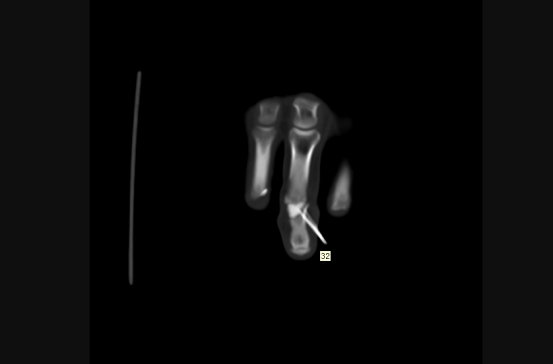

近日,45歲劉先生在工地工作時,由于操作不慎,被圓盤鋸割傷右手,導致右手腫痛、嚴重出血,到我院接受治療,經檢查發現右中指關節缺損。930日,我院手足外科團隊成功為其實施自體小關節移植修復術,在手外傷創傷修復領域邁出重要一步。

手術CT圖

“所謂自體關節移植,就是將患者自身的關節進行移植和替換,相比傳統的人工關節置換,該技術具有修復及時、沒有排異反應、治愈效果明顯等優點?!敝鞯夺t生胡明興介紹,經放射醫學科行三維CT精準動靜脈及骨重建,在麻醉科的大力支持下,通過將腳趾關節及附近血管、神經、肌肉進行移植,他們僅用一次手術就為患者完成了手指修復,不需要多次開刀,盡可能保障了患者安全。